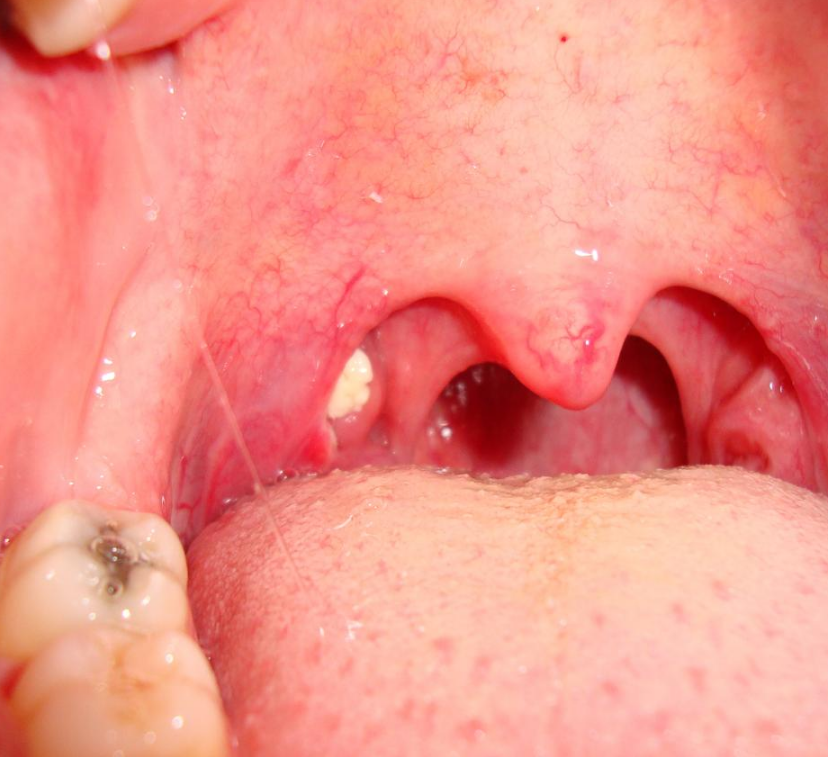

Large tonsillolith half exposed on tonsil